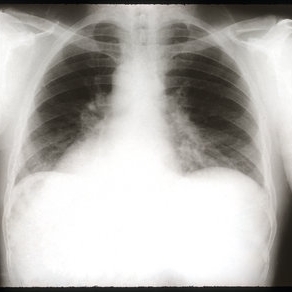

Sarcoidosis Panuveitis Slide 7

Chest x-ray revealed bihilar lymphadenopathy.

Photographer: The New York Eye & Ear Infirmary Department of Radiology

Condition/keywords: sarcoidosis panuveitis